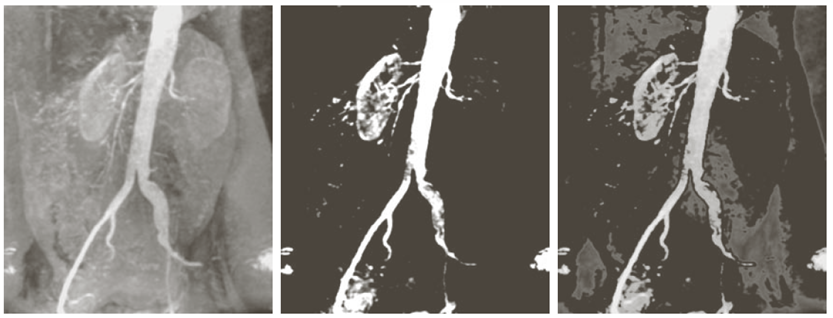

위 이미지의 가장 왼쪽이미지는 원본 영상이다. 가운데 이미지는 Binary Highlighting 방식으로 혈관 부분만 흰색, 배경은 검정색임을 볼 수 있다. 가장 오른쪽 이미지는 Preserve 방식으로 특정 영역을 black으로 만들고 혈관과 콩팥 부분은 보존하여 혈관과 콩팥을 강조하는 영상을 만들었다.